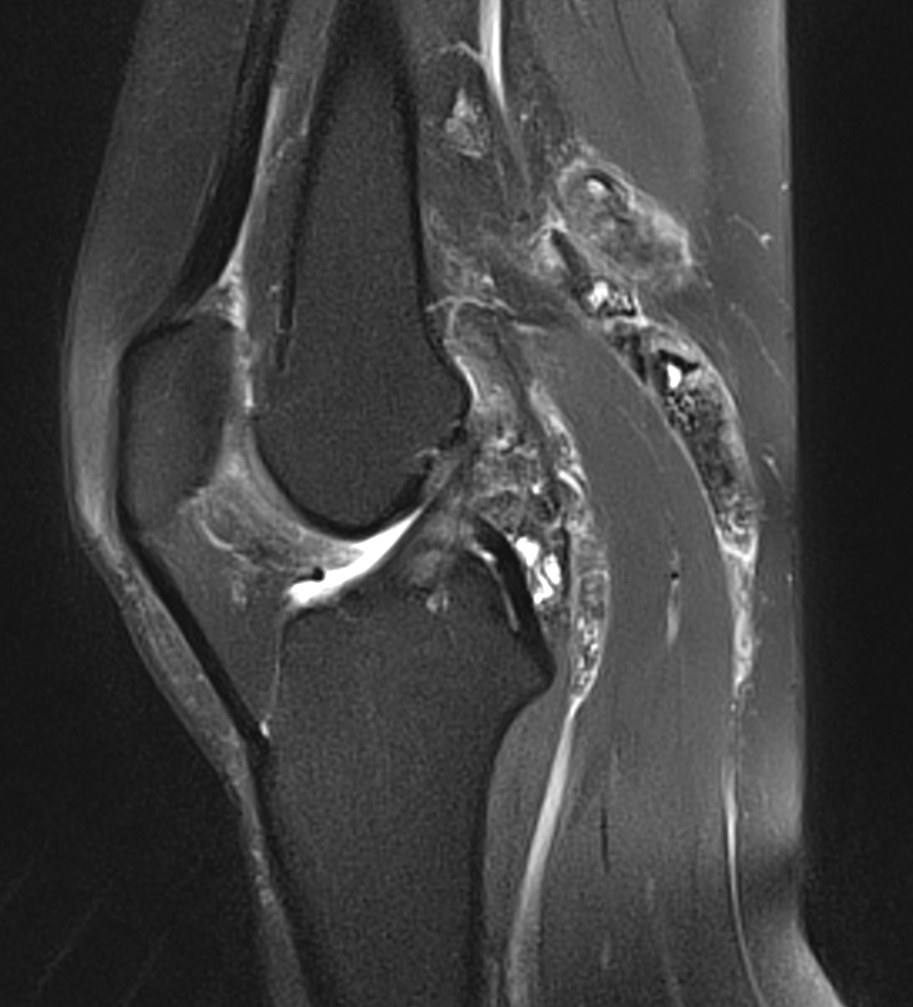

Synovite villo-nodulaire du genou

Synovite villo-nodulaire du genou 2